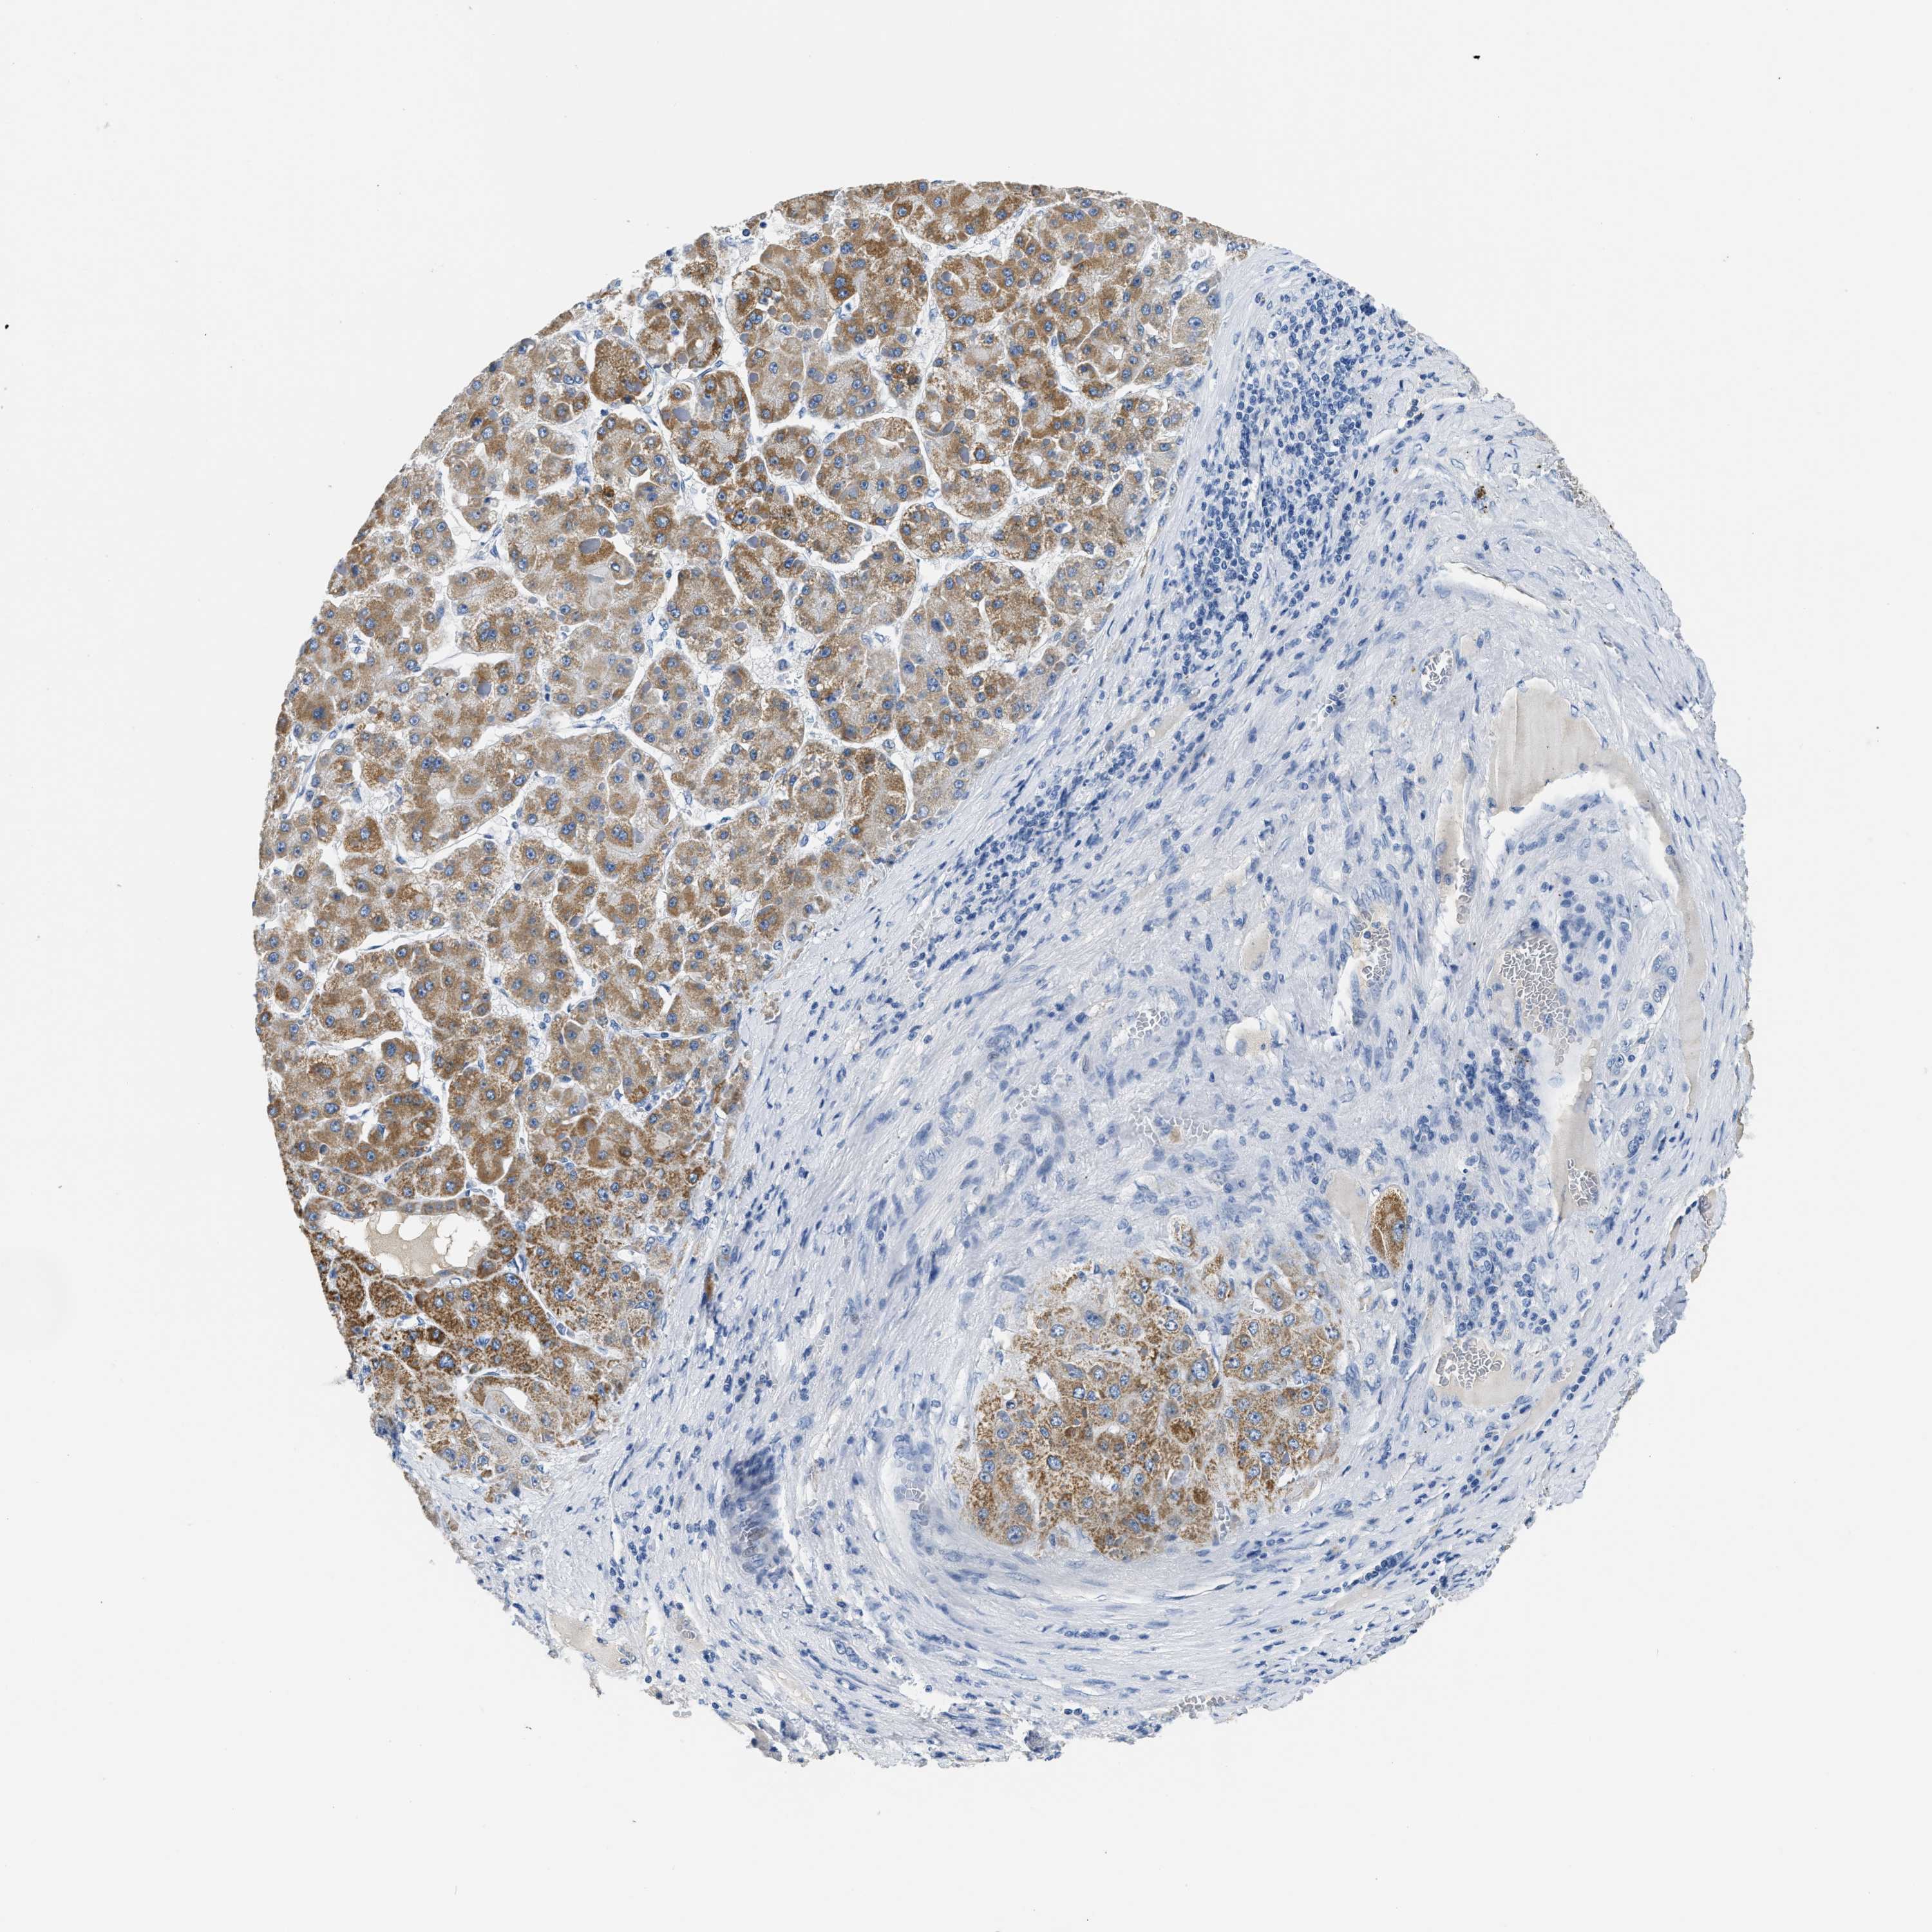

LIVER CANCER - Protein expressioni

A mouse-over function shows sample information and annotation data. Click on an image to view it in a full screen mode. Samples can be filtered based on level of antibody staining by selecting one or several of the following categories: high, medium, low and not detected. The assay and annotation is described here.

Note that samples used for immunohistochemistry by the Human Protein Atlas do not correspond to samples in the TCGA dataset.

Antibody stainingi

Antibody staining in the annotated cell types in the current human tissue is reported as not detected, low, medium, or high, based on conventional immunohistochemistry profiling in selected tissues. This score is based on the combination of the staining intensity and fraction of stained cells.

Each image is clickable and will lead to virtual microscopy that enables deeper exploration of all samples and also displays staining intensity scores, fraction scores and subcellular localization as well as patient and tissue information for each sample.

Antibody HPA051162

Antibody HPA053502

Antibody CAB018734

Staining

High

Medium

Low

Not detected

Intensity

Strong

Moderate

Weak

Negative

Quantity

>75%

75%-25%

<25%

None

Location

Nuclear

Cytoplasmic/membranous

Cytoplasmic/membranous,nuclear

Cholangiocarcinoma

Carcinoma, Hepatocellular, NOS